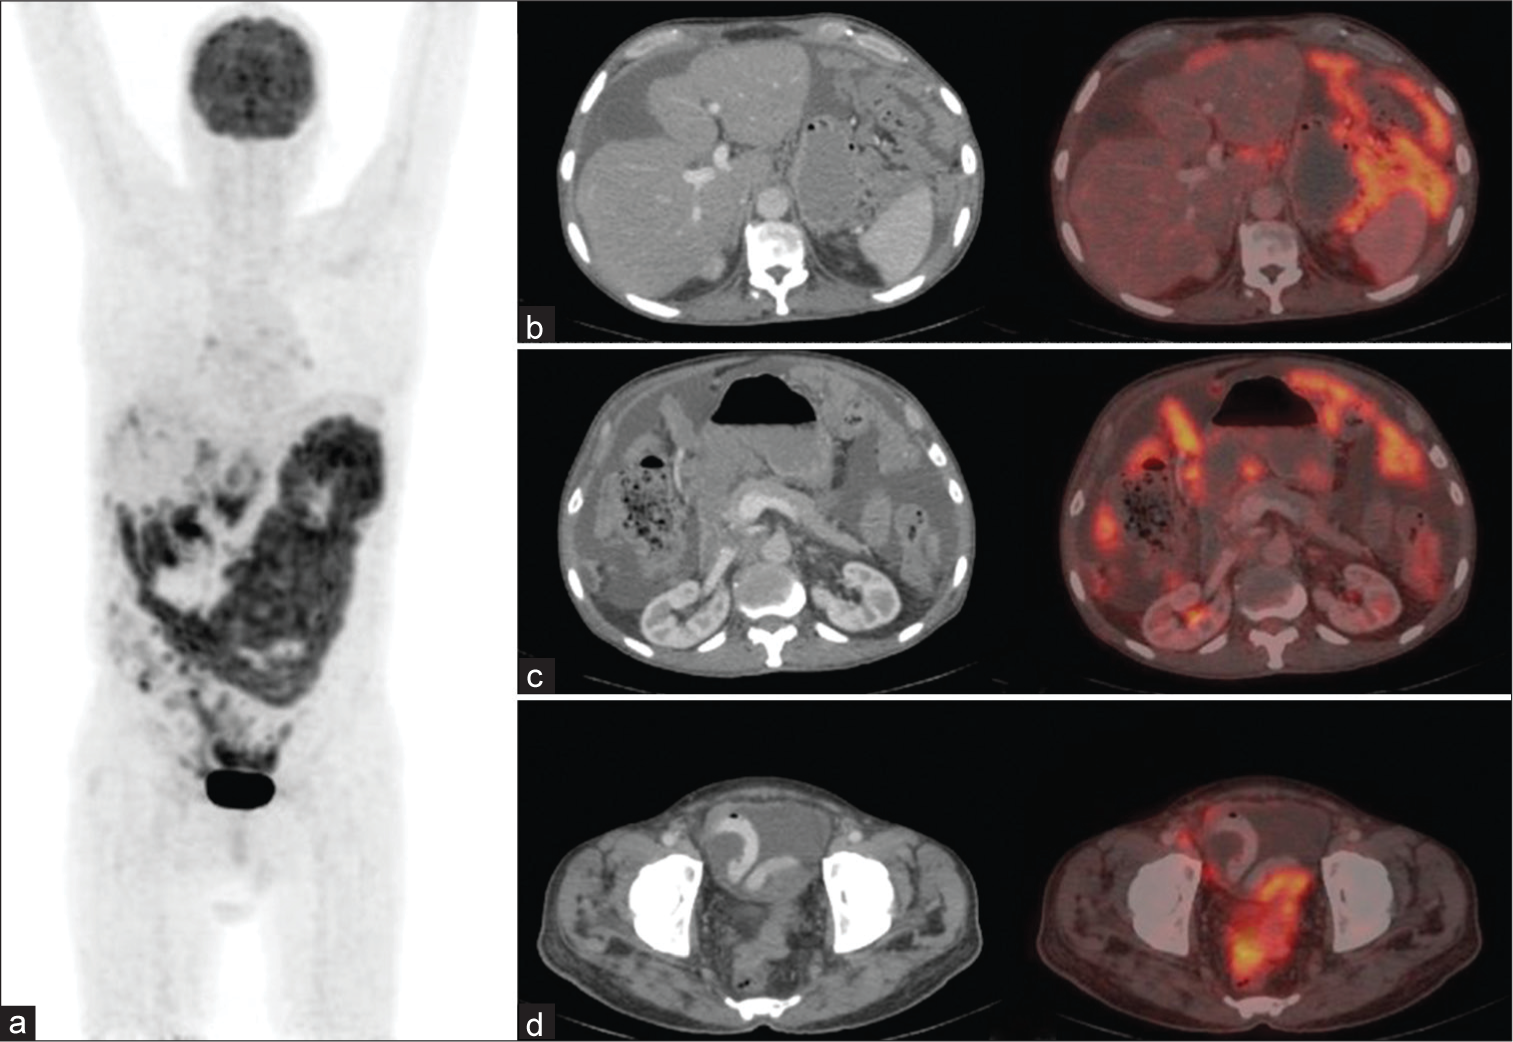

A 67-year-old male presented with complaints of abdominal heaviness, bloating, loss of appetite, and constipation for 2 months. An abdominal ultrasound revealed moderate ascites with irregular omental and peritoneal thickening. Fine-needle aspiration cytology from the omental thickening was positive for malignancy, favoring metastasis. Colonoscopy and upper gastrointestinal (GI) endos-copy were unremarkable. The patient was referred to our department for a 18F Fluorodeoxyglucose (FDG) positron emission tomography/computed tomography (PET/ CT) scan to identify the primary disease and assess subsequent staging. The scan was performed 60 min aft er the intravenous injection of 18F FDG. It revealed diffuse FDG-avid omental and peritoneal thickening with multiple serosal soft tissue deposits and lymphadenopathy in the abdomen and pelvis, along with gross ascites and pleural effusion. The GI tract, pancreas, gallbladder, and lung appeared unremarkable, raising a high suspicion for primary peritoneal carcinomatosis [Figure 1]. A subsequent biopsy and immunohistochemistry (IHC) from the peritoneal and omental thickening confirmed the diagnosis of mesothelioma, deciduoid type, with IHC markers positive for Calretinin, WT 1, CK 5/6, and PAN CK [Figures 2 and 3].

- (a) The MIP image of 18F fluorodeoxyglucose positron emission tomography-computed tomography (PET-CT) scan showing diffuse peritoneal carcinomatosis. (b,c,d) shows axial CT and fused PET-CT images of diffuse peritoneal and omental thickening, serosal soft tissue deposits, lymphadenopathy, and ascites. (b and c) Gallbladder and pancreas appear unremarkable

In this case, FDG PET/CT played a crucial role in diagnosis, staging, prognosis, and treatment selection. While cytology identified the presence of malignant cells, PET/CT revealed the full extent of disease by showing diffuse peritoneal and omental thickening, serosal soft tissue deposits, lymphadenopathy, ascites, and pleural effusion. In addition, it also helped exclude other primary sites. The absence of significant metabolic activity or any lesion in the GI tract, pancreas, gallbladder, and lungs increased suspicion for primary peritoneal carcinomatosis rather than metastasis from another malignancy. This was further corroborated with no abnormality detected in colonoscopy and upper GI endoscopy and confirmed by biopsy and IHC markers consistent with mesothelioma. The scan also demonstrated a maximum standardized uptake value of 6.6, suggesting more aggressive disease with a poorer prognosis.[6,9,10]